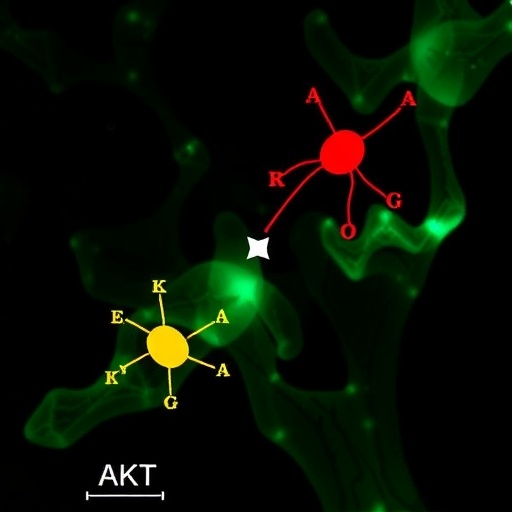

In a groundbreaking study published in the Journal of Ovarian Research, researchers have delved into the complexities of ovarian hyperandrogenism, a condition predominantly seen in women with polycystic ovary syndrome (PCOS). This research offers a novel perspective on how slight molecular alterations can lead to significant hormonal imbalances, resulting in conditions like infertility, metabolic syndrome, and even psychological issues in women. The team led by Zhang, Lin, and Lin utilized a cutting-edge technique known as single-cell transcriptomics to reveal the intricate interplay among various cellular pathways, highlighting an essential axis composed of AKT, LONP1, and STAR.

One remarkable finding from this research is the prominent role of the AKT signaling pathway, traditionally associated with cell survival and metabolism. In the context of ovarian hyperandrogenism, the study illustrated that the activation of AKT leads to increased production of androgens, exacerbating the symptoms of PCOS. The overactivation of this pathway points to a likely target for therapeutic interventions that could help manage symptoms or even reverse the impacts of the disease.

In parallel with the exploration of AKT, the research illuminated the significance of LONP1, an intriguing gene linked to mitochondrial function. LONP1 is critical for maintaining cellular energy balance and managing oxidative stress, factors that are vital for the proper functioning of ovarian cells. The study indicated that dysregulation of LONP1 could lead to mitochondrial dysfunction, contributing to the overall hormonal imbalance and reproductive challenges faced by women with PCOS.

Furthermore, STAR (steroidogenic acute regulatory protein) emerged as another key player in this dynamic triad. STAR is essential for the transport of cholesterol, the precursor for steroid hormone synthesis, into the mitochondria. The findings reinforce the notion that impairments in STAR function could be a fundamental factor driving elevated androgen levels, presenting another avenue for potential therapeutic strategies targeting PCOS and its associated symptoms.

Building on their discoveries, the research team emphasized the potential for developing targeted therapies that focus on this newly identified AKT-LONP1-STAR axis. By modulating these pathways, clinicians might be able to improve the metabolic and reproductive outcomes for women suffering from PCOS. The concept of personalized medicine, where treatments are tailored based on specific molecular profiles, becomes increasingly feasible with such detailed understandings of the disease mechanisms.

In summary, this innovative study harnesses the power of single-cell transcriptomics to offer a fresh perspective on ovarian hyperandrogenism in PCOS. By characterizing the critical AKT-LONP1-STAR axis, the research not only sheds light on the underlying mechanisms of the condition but also opens new avenues for targeted therapies, improving the lives of millions of women grappling with PCOS.